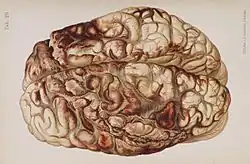

| An illustration of a brain after an "encircling" gunshot wound showing the pattern of injury caused by the bullet's path | |